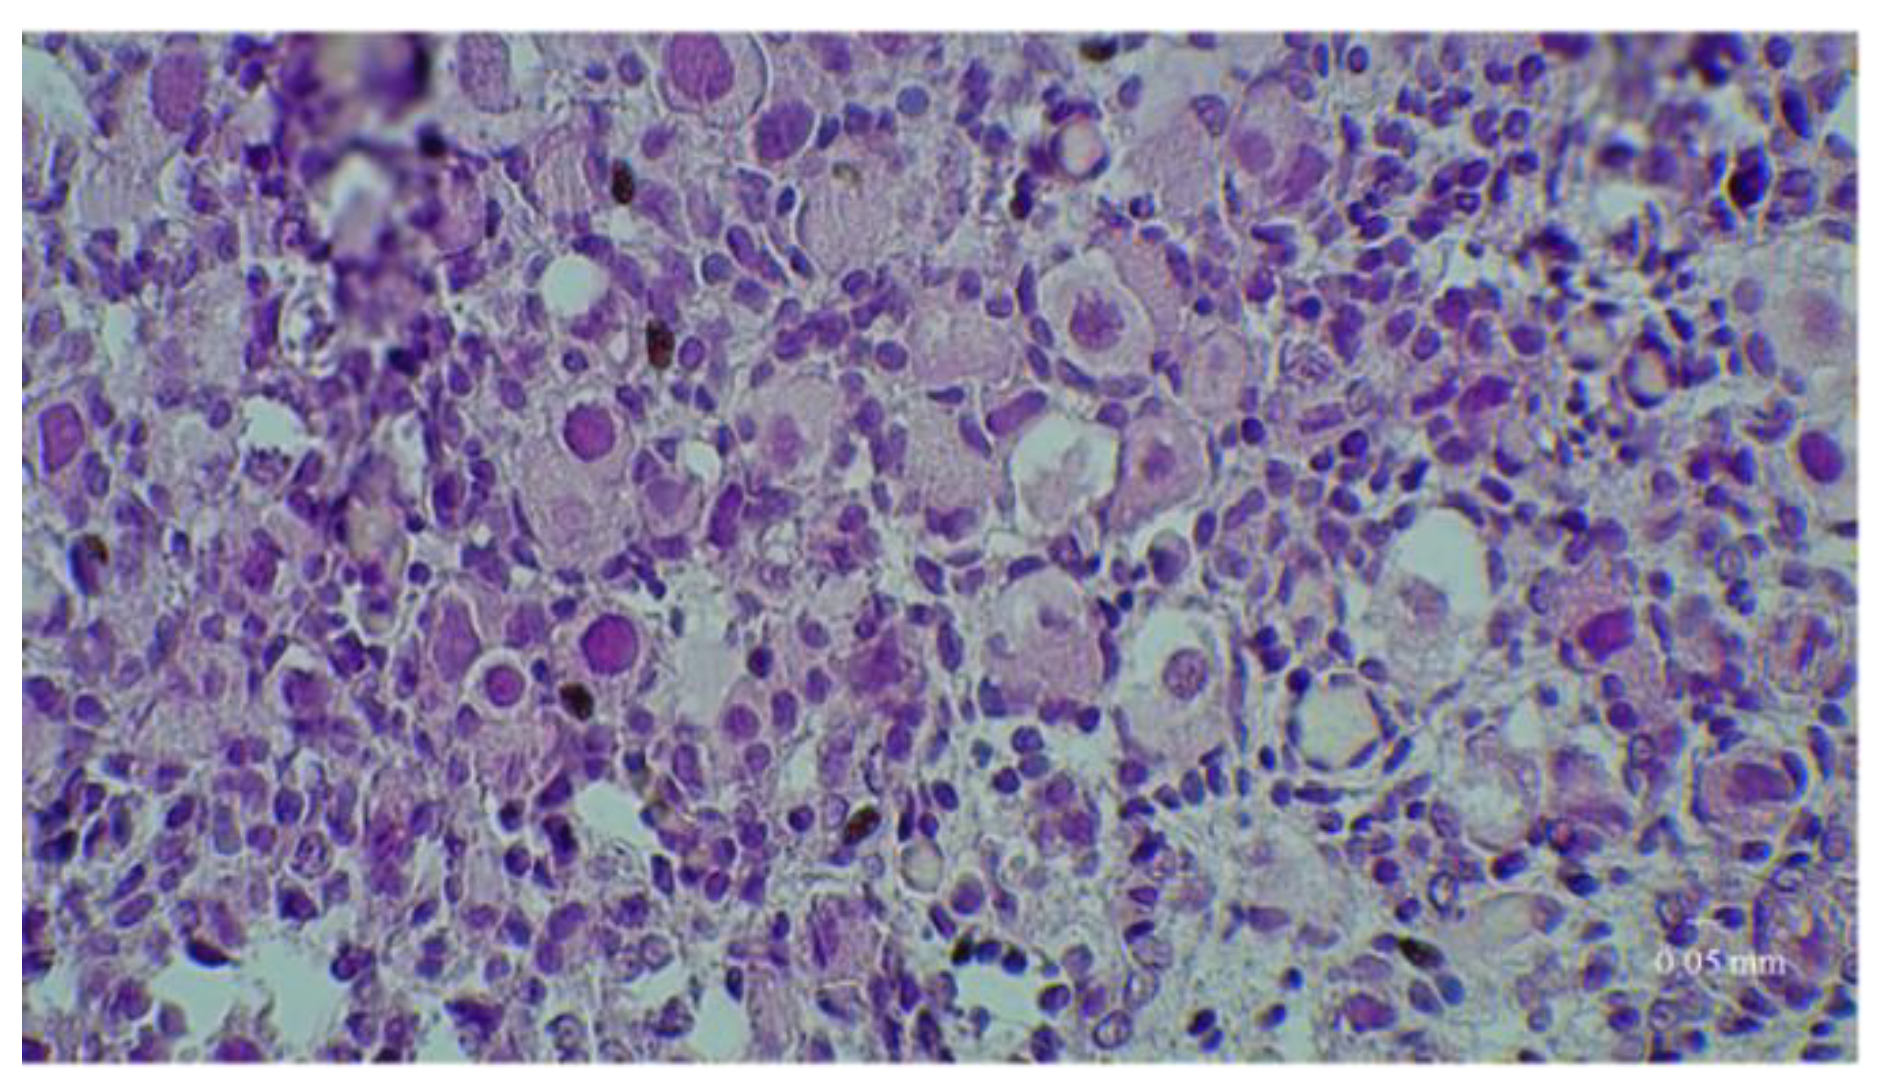

2.4. Histological Analyses

3. Results

3.1. Results of the First Set of Analyses with Intact Follicles as Denominator

3.2. Results of the Second Set of Analyses with All Present Follicles as Denominator

3.3. Immunostaining for Cell Apoptosis